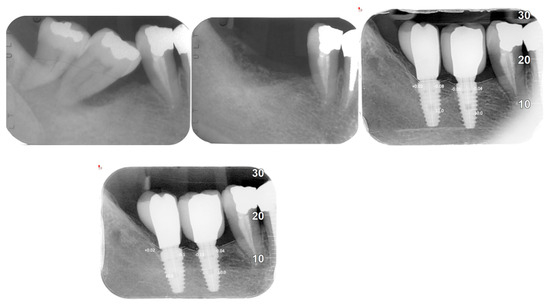

| Evaluation Methods | Orthopantomograms (OPG), cone beam computed tomography (CBCT), intraoral radiographs, clinical examinations |

| Implant Success Rate | 100% after 4 years |

| Peri-implant Bone Loss | Mean: 0.1208 mm (±0.1307) |

| Mesial Bone Loss | 0.14302 mm (±0.0107) |

| Distal Bone Loss | 0.09934 mm (±0.0143) |

| AVERAGE BONE LOSS | 0.1208 + −0.1307 |

| Mesial bone loss | 0.14302 + −0.0107 |

| Distal bone loss | 0.09934 + −0.0143 |